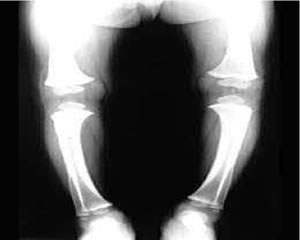

Diagnosi per immagini

Le tipiche alterazioni scheletriche descritte corrispondono a delle chiare immagini radiografiche che permettono una facile diagnosi.

Le alterazioni principali riguardano tutte e tre le porzioni delle ossa lunghe.

La cartilagine epifisaria si presenta ispessita, a forma di coppa e radiotrasparente a livello dell'incontro con la metafisi, la quale a sua volta possiede una struttura trabecolare con disegno alterato che si può evidenziare già nel primo anno di vita a carico dell'ulna e del radio.

Le alterazioni diafisarie, invece, sono date da un assottigliamento corticale e da un incurvamento dell'asse dell'osso.